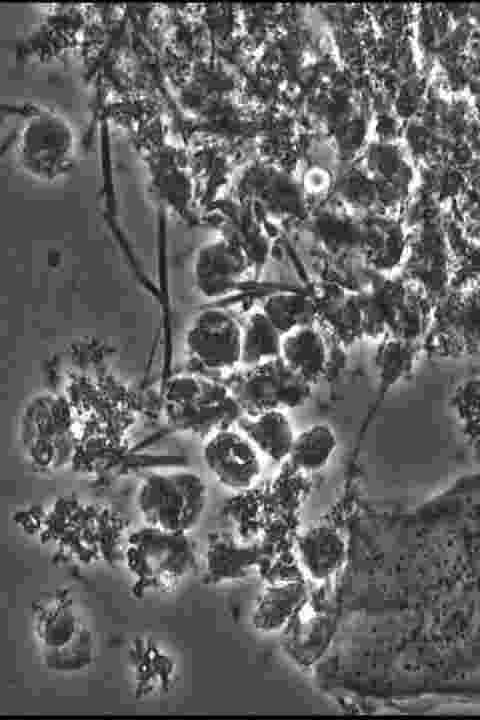

歯周病の患者の歯垢を採取し、顕微鏡を覗くと様々な細菌が見えます。口腔内には300種類以上の細菌が住んでいますが、その中の20種類は歯周病に関係のある菌です。中でもスピロヘータというかなり悪い菌が存在します。

スピロヘータ感染で発症する病気には、梅毒、回帰熱、歯周病などがあります。顕微鏡で見ると細長く、回転運動やくねらせる動きをしています。(かなり気持ち悪いです)感染経路としては、不衛生な環境から感染することが多いです。パートナーの方が重度の歯周病だと、スピロヘータを相手にも感染させてしまう可能性があります。よく磨かけている方でも、なかなか症状が治まらない場合

ご飯を食べた後に歯についている食べかす(プラーク)を顕微鏡で覗くと…

このように、カビや菌が潜んでいるのです。

このカビや菌を減らすことで、歯周病の予防や進行を遅くすることができるのです。

この顕微鏡で確認すれば、どんな菌がいるかがわかり、歯磨きにも更に力が入るのではないでしょうか?

当医院でもこの位相差顕微鏡を導入致しました!